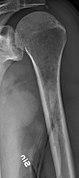

Medical imaging

The diagnostic examination of a person with suspected multiple myeloma typically includes a skeletal survey. This is a series of X-rays of the skull, axial skeleton, and proximal long bones. Myeloma activity sometimes appears as "lytic lesions" (with local disappearance of normal bone due to resorption). And on the skull X-ray as "punched-out lesions" (pepper-pot skull). Lesions may also be sclerotic, which is seen as radiodense.[52] Overall, the radiodensity of myeloma is between −30 and 120 Hounsfield units (HU).[53] Magnetic resonance imaging is more sensitive than simple X-rays in the detection of lytic lesions, and may supersede a skeletal survey, especially when vertebral disease is suspected. Occasionally, a CT scan is performed to measure the size of soft-tissue plasmacytomas. Bone scans are typically not of any additional value in the workup of people with myeloma (no new bone formation; lytic lesions not well visualized on bone scan).